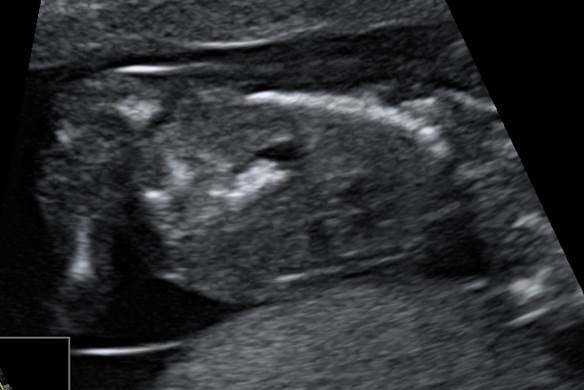

Вопрос 4

КТР 65 мм. Какой диагноз? Рекомендации?